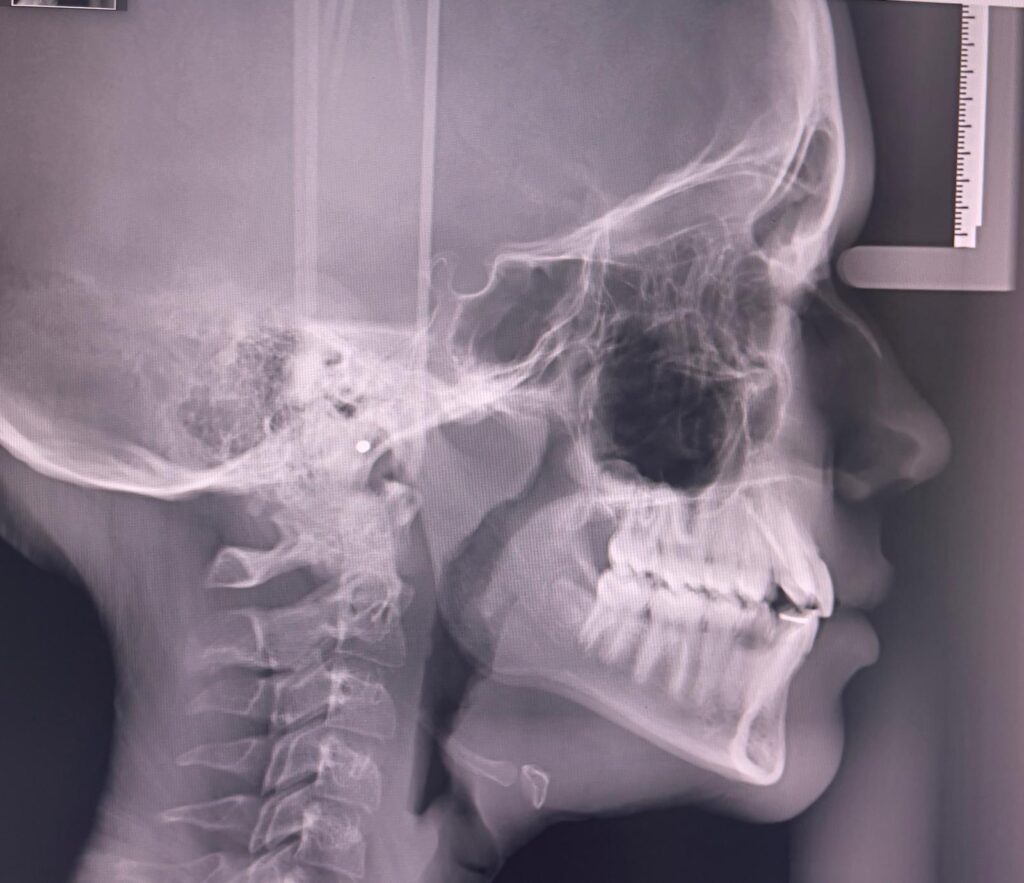

Zdjęcie cefalometryczne

Zdjęcie cefalometryczne to badanie rentgenowskie wykorzystywane głównie w ortodoncji i chirurgii szczękowo-twarzowej. Pozwala na ocenę relacji między zębami, kośćmi szczęki i żuchwy. Jest nieocenione przy diagnozie wad zgryzu, planowaniu leczenia aparatami ortodontycznymi oraz przed zabiegami chirurgicznymi. Dzięki dokładnym pomiarom i precyzyjnemu odwzorowaniu struktur kostnych, nasi lekarze dentyści mogą tworzyć indywidualne plany leczenia, minimalizując ryzyko komplikacji oraz maksymalizując efekty estetyczne i funkcjonalne.